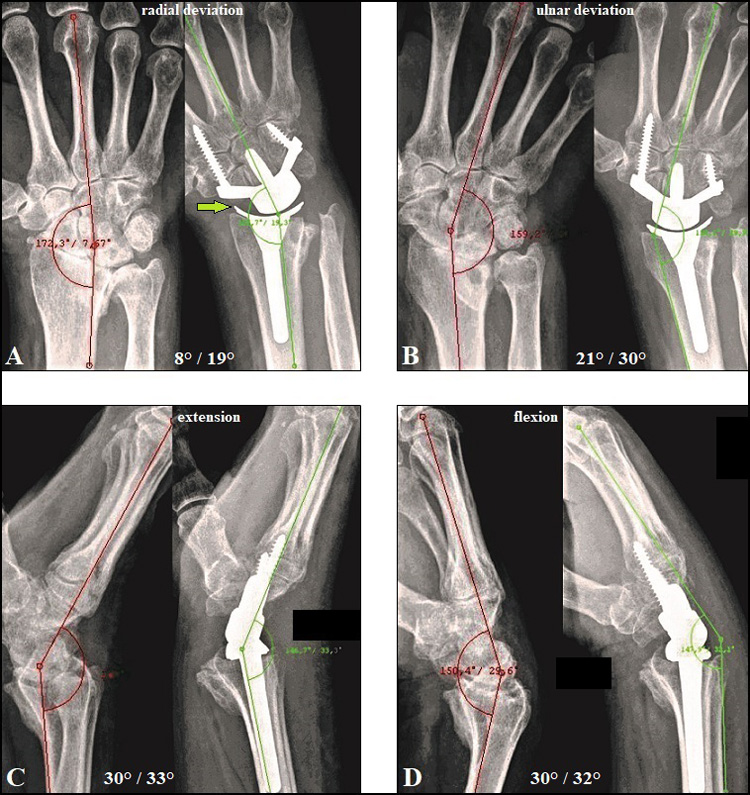

Four-corner fusion of the wrist: clinical and radiographic outcome of …

Four-corner fusion of the wrist: clinical and radiographic outcome of …

Relationship Between Wrist Motion and Capitolunate Reduction in Four …